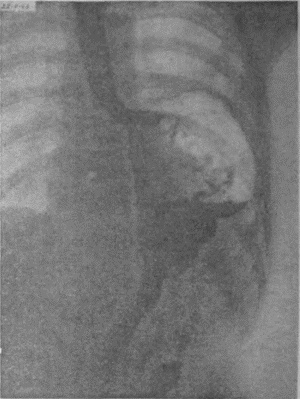

Если при локальном раке кардии и нижнего конца пищевода можно ограничиться все же экономной резекцией фундального отдела, то при более обширном раке или опухолях, захвативших немалую часть верхней трети малой кривизны, иногда возникает вопрос о целесообразности оставления антральной культи взамен тотальной гастрэктомии с трансторакальным соустьем пищевода и тощей кишки. Мотивы для этого могут быть двоякие. Первый и, конечно, главный — это радикальность самой резекции. Вопрос ставится так: да стоит ли сохранять антральный отдел желудка, рискуя, что в нем останутся пока еще невидимые раковые очаги; не вернее ли убрать весь желудок целиком и анастомозировать с тощей кишкой? Не создает ли тотальная гастрэктомия все же большую гарантию от рецидива? Я несколько раз видел отчетливую диссеминацию раковых узелков по передней и задней стенке желудка в радиальных направлениях, исходящую от строго локальной карциномы кардии. Это понуждало резецировать желудок в дистальном направлении весьма широко, оставляя лишь совсем маленькую антральную культю, которую удавалось все же подвести вверх в средостение и там легко анастомозировать с пищеводом тотчас ниже дуги аорты. На прилагаемых рентгенограммах (рис. 95—102) можно видеть, что небольшая культя желудка хорошо подтягивается кверху и прекрасно располагается в заднем средостении на месте иссеченного пищевода. Но каждый раз остается и тревожная мысль, как бы не получилось рецидива именно в этой сохраненной части желудка, поскольку рак проявил склонность к узелковому распространению по самой желудочной стенке. Второе соображение, которое выдвигает мысли о тотальной гастрэктомии, это опасение, что содержимое оставляемой дистальной половины желудка после пересечения обоих блуждающих нервов будет плохо эвакуироваться и тем доставит серьезные неприятности в ближайшем послеоперационном периоде. На моем личном опыте я пока еще не имел такого осложнения, но в нашей клинике однажды наблюдался больной, у которого эвакуация содержимого из оставленной антральной культи была чрезвычайно плохой в течение многих дней после операции. При этом создавалось впечатление, что полная атония оставленной части тела желудка сочетается с выраженным спазмом привратника, который не пропускал принятого бария в двенадцатиперстную кишку. Хотя, в конце концов, все наладилось и больной выписался в хорошем состоянии, однако тревог с ним было очень много. ![]() Рис. 95. ![]() Рис. 96. ![]() Рис. 97. ![]() Рис. 98. ![]() Рис. 99. ![]() Рис. 100. ![]() Рис. 101. ![]() Рис. 102. За сохранение антральной половины желудка и использование ее для прямого анастомоза с пищеводом говорит соблазнительно хорошая васкуляризация этой дистальной половины из сохраненных магистралей: аа. gastro-epiploica dextra et gastrica dextra. Насколько внимательно надо оценивать пригодность фундального отдела после лигирования обеих левых желудочных магистралей и всех vasa gastricae breves при самых высоких, надаортальных соустьях после экстирпаций среднего пищевода, настолько же после резекций проксимальной трети или половины желудка остающаяся дистальная часть превосходно васкуляризируется правыми артериальными магистралями. А это обстоятельство надежнее всего обеспечивает быстрое и прочное сращение по линии желудочно-пищеводного соустья, т. е. наиболее решающий этап всей операции. Мне могут возразить, что, анастомозируя пищевод с тощей кишкой, мы пользуемся органом, не менее богатым по кровоснабжению. Это верно, но поперечник тощей кишки не дает столько простора и пластического материала, сколько его имеется даже на короткой, но широкой антральной культе. Благодаря ширине культи имеется возможность после окончания двухрядного поперечного соустья укрыть дополнительно всю переднюю полуокружность анастомоза, сдвигая и сшивая над ним складки большой и малой кривизны. Прием этот чрезвычайно повышает прочность и герметизм соустья. А риск недостаточности последнего является главной опасностью всех подобных операций. При анастомозах с дистальной половиной желудка мы до сих пор осложнений еще не имели; зато три раза на десяток высоких резекций пищевода и анастомозов с фундальным отделом мы столкнулись с частичной недостаточностью соустья. В двух из этих случаев дело закончилось благополучно, и после вскрытия и дренажа ограниченных эмпием и срочного наложения подвесных энтеростомий для кормления пищевые свищи закрылись самостоятельно и довольно быстро. Но третий больной, врач 52 лет, хорошо перенеся надаортальную резекцию пищевода, постепенно угас, истощаясь из-за чресплеврального свища, получившегося вследствие недостаточности пищеводно-желудочного соустья. Повторяю, не только васкуляризация, но и форма оставляемой желудочной культи предопределяют качество и надежность анастомоза. Поэтому и при наложении раздавливающих гразеровских зажимов на желудок мы стремимся получить не длинную, узкую культю, а широкую, хотя бы за счет ее укорочения. Поднять высоко в средостение короткую культю можно без натяжения; зато ширина ее позволит сделать двойную боковую запашку поверх передней части законченного соустья с пищеводом. Чтобы еще уменьшить натяжение на линии анастомоза, после окончания последнего желудочную культю тщательно укладывают в заднее средостение и пришивают в нескольких местах к краям левой медиастинальной плевры. Наконец, совершенно обязательно пришить желудок к отверстию, оставляемому для него в ушиваемом разрезе диафрагмы. Напомню, что в самом начале операции, как только была вскрыта плевральная полость, n. phrenicus, всегда отчетливо видимый при переходе с перикарда на верхний купол диафрагмы, анестезируется инъекцией новокаина и раздавливается торзионным зажимом. Это создает неподвижность левой половины диафрагмы не только на время вмешательства, но и в течение нескольких месяцев после операции; таким образом, желудочная культя, вшитая в отверстие неподвижной диафрагмы, получает надежную опору и тем дополнительно исключается возможность натяжения в швах анастомоза. |